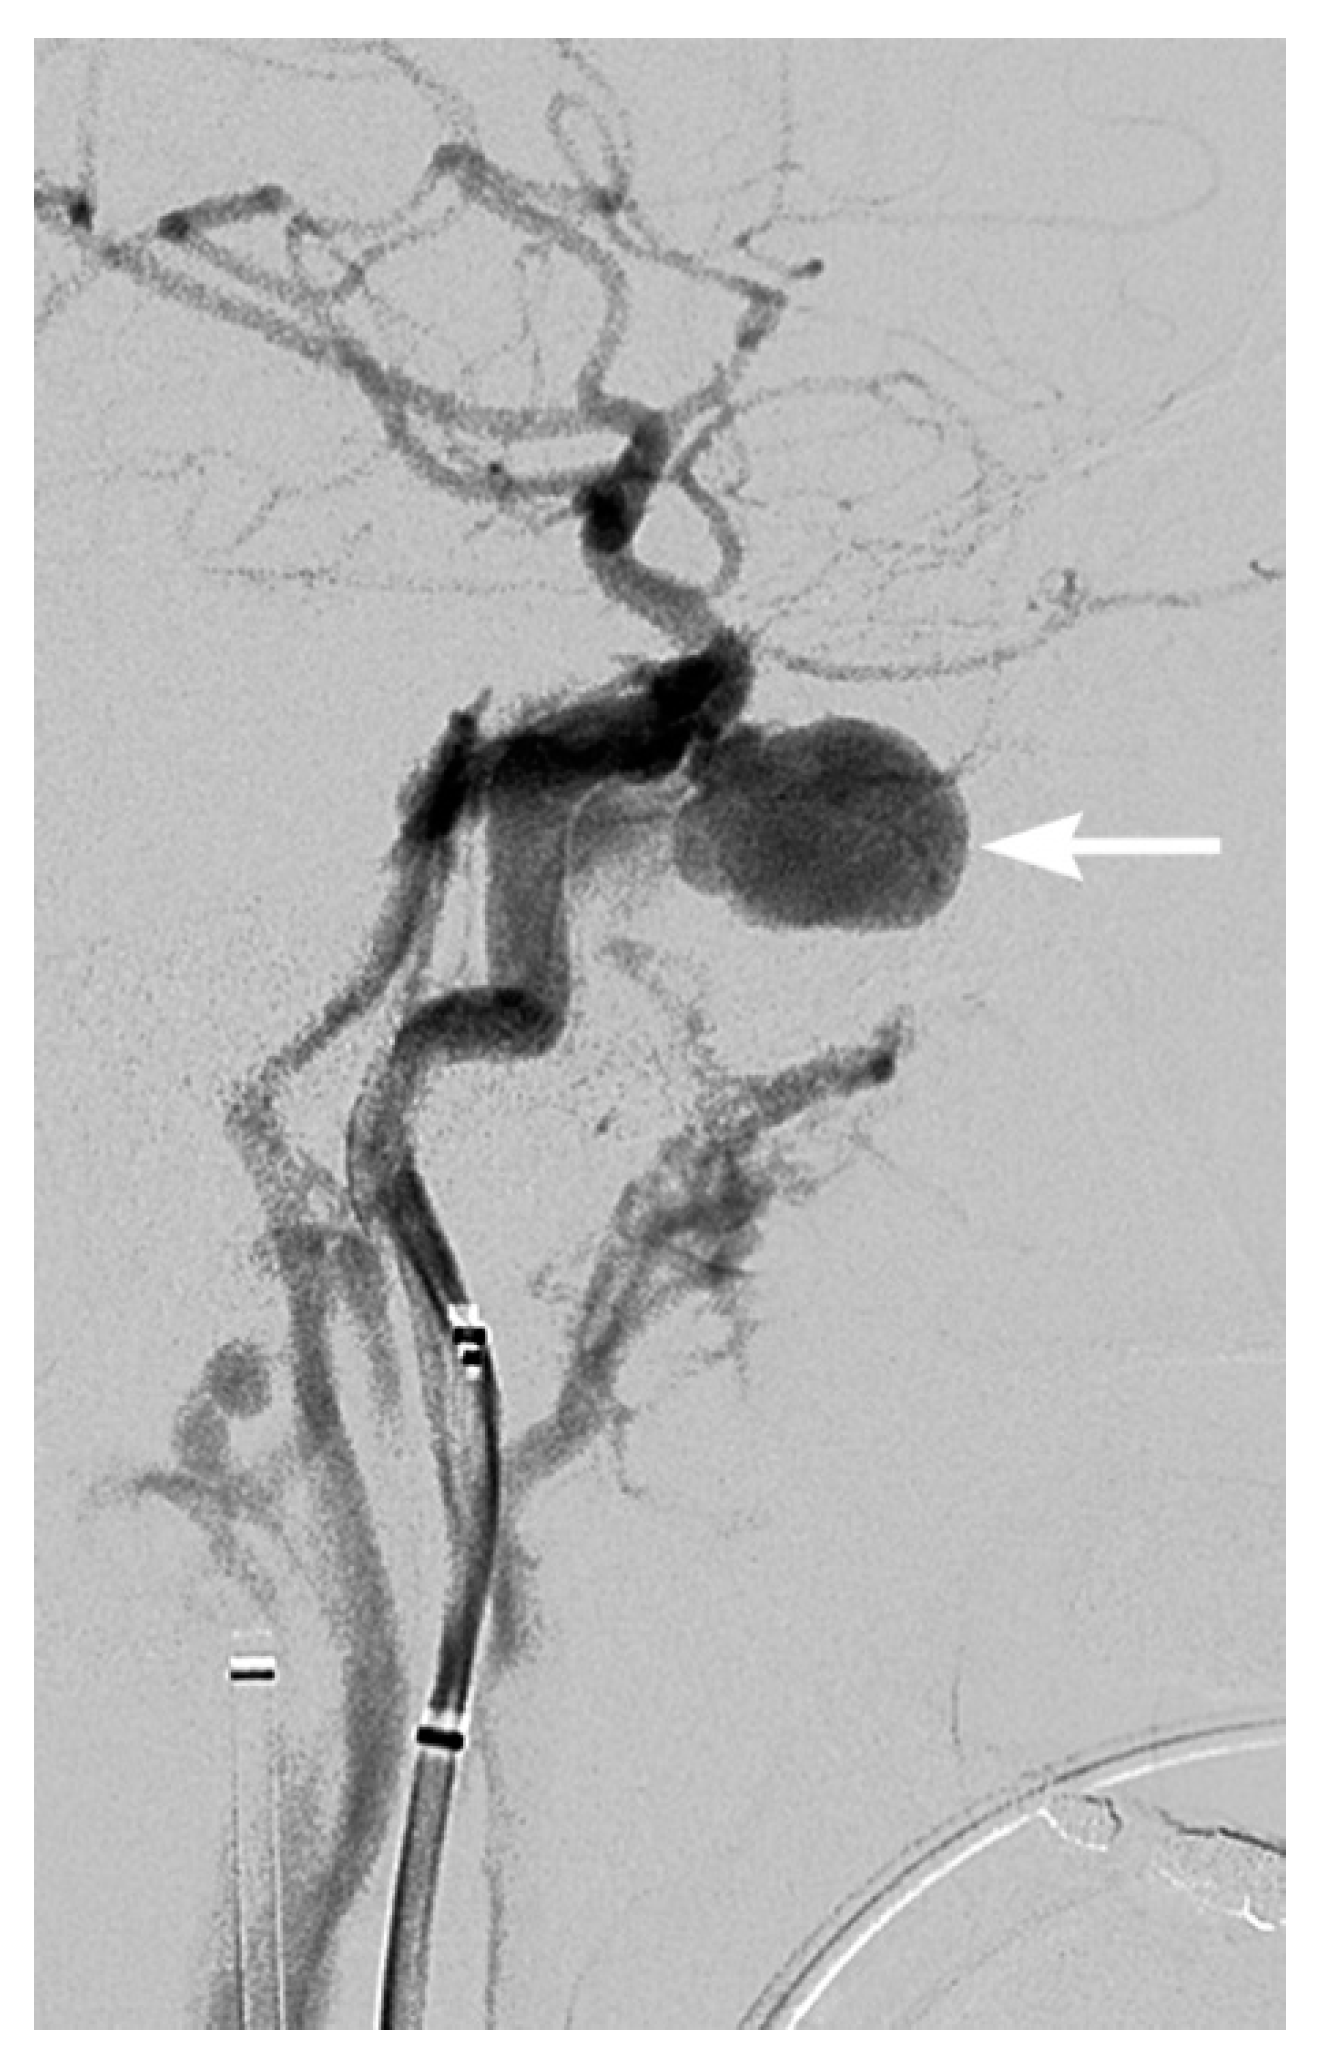

3. Imaging Findings of Arterial Injury